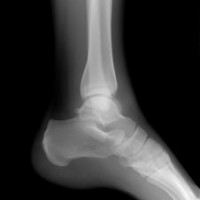

TBC tulang adalah penyakit yang disebabkan oleh virus mycobacterium tuberculosa. Virus yang umumnya menyerang bagian tubuh paru - paru ini juga dapat menyerang bagian tubuh lainnya seprti tulang, selaput otak (meningitis), kulit dan organ lainnya. Penyebaran virus ini adalah lewat udara dan masuk melalui saluran pernapasan. Masa inkubasi virus … [Read more...]